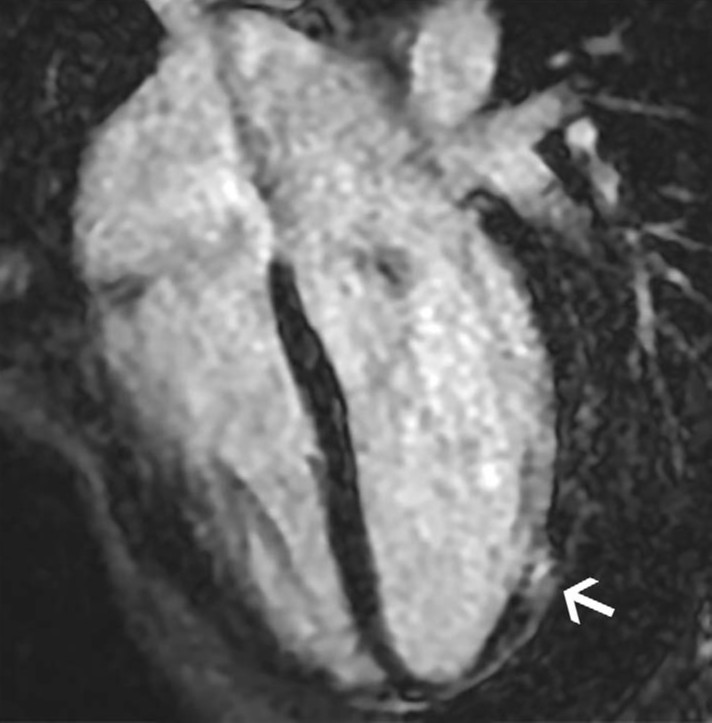

La TC cardíaca es especialmente valiosa cuando la pregunta clínica apunta a coronarias: anomalías congénitas, trayectos interarteriales o enfermedad aterosclerótica en atletas mayores. El artículo remarca que la angiografía por TC es altamente precisa para evaluar anomalías coronarias y enfermedad coronaria, y que en atletas master el territorio coronario se vuelve central porque la enfermedad aterosclerótica pasa a ser la principal causa de muerte súbita. En este grupo, la TC no solo diagnostica: también estratifica riesgo.

FIBROSIS, EDEMA Y CORONARIAS ANÓMALAS NO SON HALLAZGOS MENORES

Dos escenarios del paper concentran el mayor valor narrativo del blog. Primero, la miocarditis: la combinación de LGE subepicárdico o mesomiocárdico con elevación de T1 y T2 cumple criterios de Lake Louise y redefine temporalidad, riesgo y retorno al deporte. Segundo, las anomalías coronarias: el origen anómalo con trayecto interarterial e intramural puede ser silente en reposo, pero volverse crítico durante el ejercicio. El artículo subraya que estas anomalías se asocian con un riesgo 79 veces mayor de arritmia con el esfuerzo. Esa es la diferencia entre una imagen interesante y una imagen clínicamente decisiva.